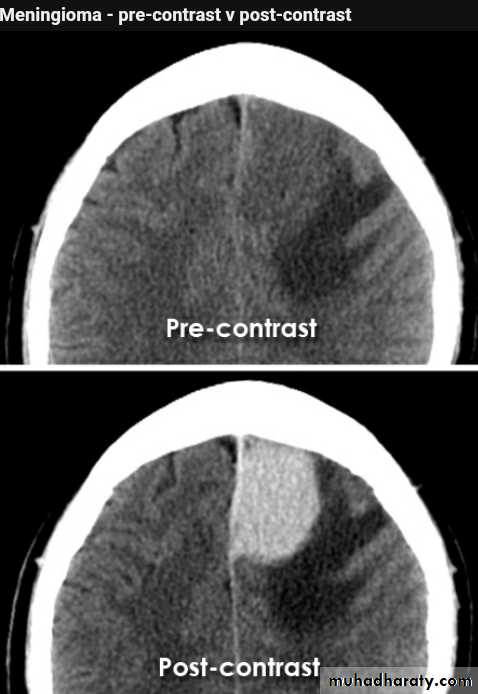

Meningioma

Benign tumor arise from the arachnid cells of the meningeal covering of the brain are most common primary intracranial neoplasm

Usually present in middle age female

it is well defined extra axial , located mainly at the convexity of the skull periphery

CT finding

meningioma presented as isodense area or slightly hyper density area with surrounded crescent of hypo density ( csf cap ) post contrast injection the lesion enhance homogeneously with enhancing Dural tail .

20 % show calcification

hyperostosis & thickening of the near by bony part of the skull & diplioc space .

it may be associated with little or no peri focal edema .

if the lesion associated with central necrosis with large perifocal edema meningio sarcoma should be excluded .